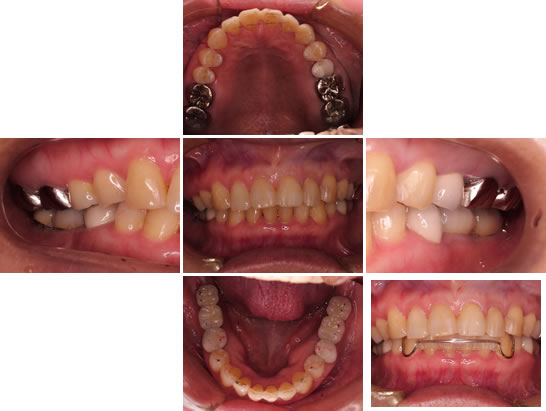

インプラントが骨と結合し、差し歯が入れられる状態になった所で、差し歯・インプラントの型を採取し、噛み合わせの平面を整えるために、フェイスボウというものを採取した状態

です。

差し歯が入った状態

上下の臼歯部に差し歯が入った状態です。これで、バーチカルストップという物が付与され、臼歯部の咬合が安定しました。

下顎の矯正治療開始

上下の臼歯部に差し歯が入ったため臼歯部の噛み合わせが安定したので下顎の矯正を開始しました。

治療完了

下顎矯正が終了した状態です。上顎の隙間は、コンポジットレジンという樹脂を用いて隙間をなくしました。右下の写真は、矯正後の後戻りを防止する、リテーナーという装置を入れた状態です。